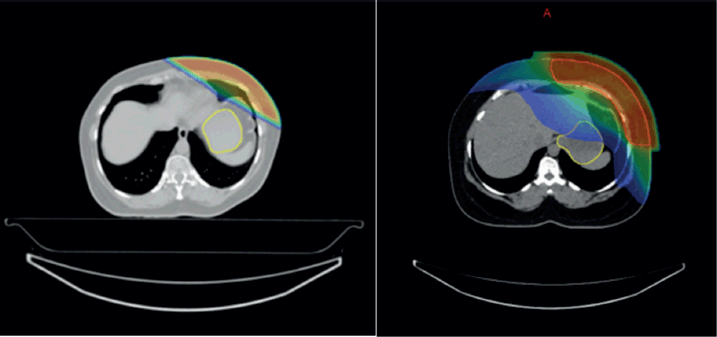

Overall, the significant factors influencing acute upper GI toxicity included radiation technique, RT dose and dose to stomach (D10 cc, D30 cc and D60 cc). Importantly, left chest wall or breast irradiation with or without RNI during FB was associated with a significantly higher risk of GI toxicity compared to DIBH, which holds a significant negative correlation implying a protective effect and helps in reducing GI toxicity (p = 0.035) (Supplementary

Figures 1a,b and 2a,b). Additionally, a positive correlation was found between larger PTV volume and the risk of developing acute upper GI toxicity (p = 0.036).

Supplementary Figure 1. (a and b): Axial CT scan showing stomach position in FB (VMAT Technique), Figure 3b: showing stomach position in DIBH (VMAT Technique).